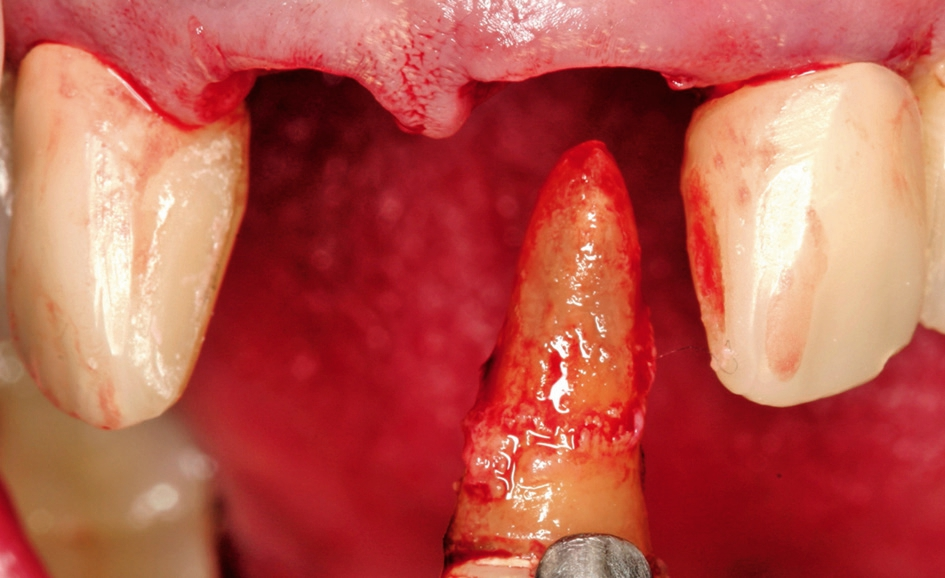

Nach Extraktion aller vier Schneidezähne (Abb. 2 und 3) zeigte sich ein massiver Knochendefekt mit Verlust der bukkalen Wand (Abb. 4). Der Behandlungsplan sah eine Augmentation und Sofortimplantation mittels Knochenringtechnik der Zähne 12 und 22 vor. Die Extraktionsalveolen der Zähne 11 und 12 sollten mit Knochen-Schleimhaut-Transplantaten aus der tuber maxillae erhalten werden, da zwischen Implantat und ovate Pontik nach Socket Preservation in der Regel eine schönere Papille zu erwarten ist.

Nach Extraktion der Zähne 12, 22, 11, 21 wurde mit dem Behandlungsprotokoll für maxgraft® bonering begonnen. Nach Pilotbohrung zur Festlegung der Implantatposition wurde mit einem 6 mm Trepan die Augmentationsstelle des maxgraft® bonerings vorbereitet (Abb. 5). Danach folgte das Planieren des Ringbettes mit einem 6 mm Planator, um ein flaches Ringbett zu generieren (Abb. 6).